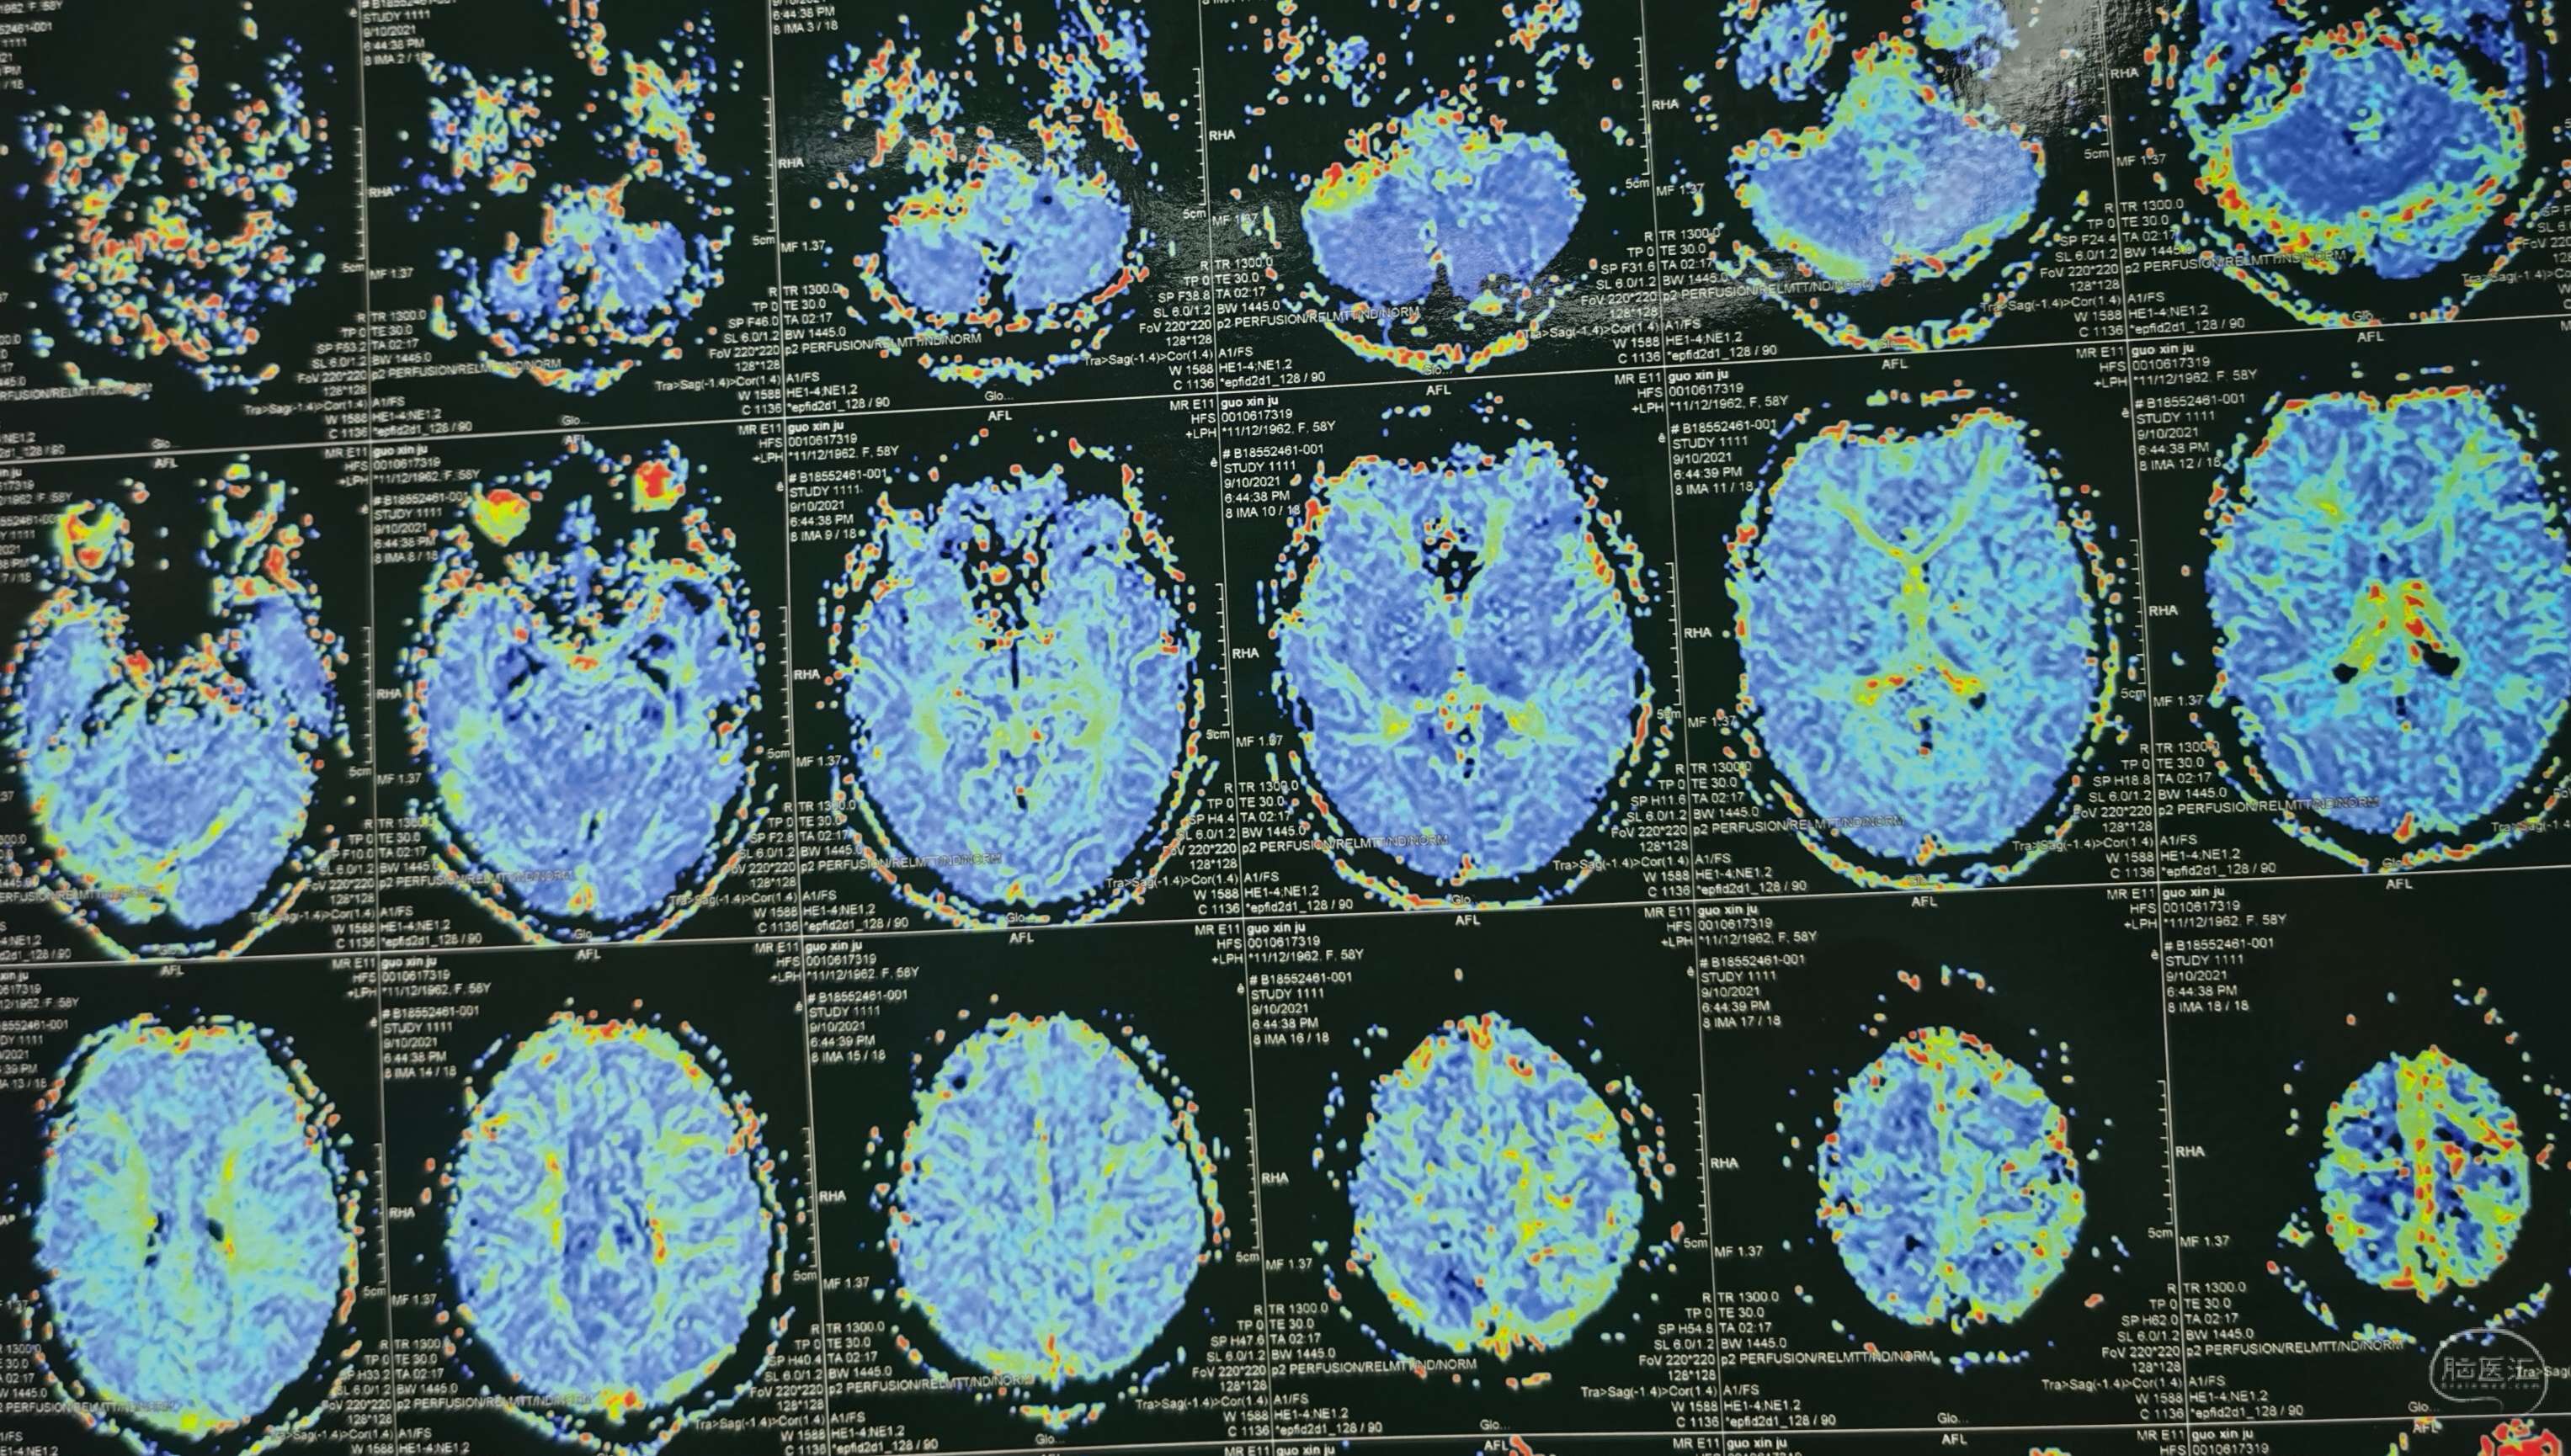

磁共振灌注提示:左侧大脑半球低灌注改变。

磁共振灌注提示:双侧大脑半球低灌注改变。